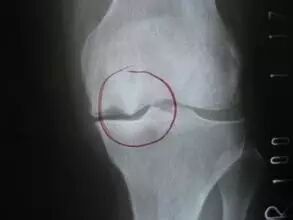

骨刺临床上称为骨质增生,多发于中年以上。这是因为随着年龄的增长,骨关节也会逐渐退化,当骨头与软组织接触的地方因长期承受压力、拉力、损伤,造成关节间的软骨渐渐失去水分与弹性,骨头与骨头磨损,人体为了减小骨关节之间的压力,在骨关节边缘上自然而然就会增生一部分来减少这个压力。它本质上是人体生理上的代偿功能,是人体为适应力的变化而产生的一种自我保护反应。

对晚期病例,如果关节出现畸形和药物不能缓解的疼痛,在全身情况能耐受手术的条件下。这时可选择手术切除骨刺、关节成形术、关节融合术或人工关节置换术。